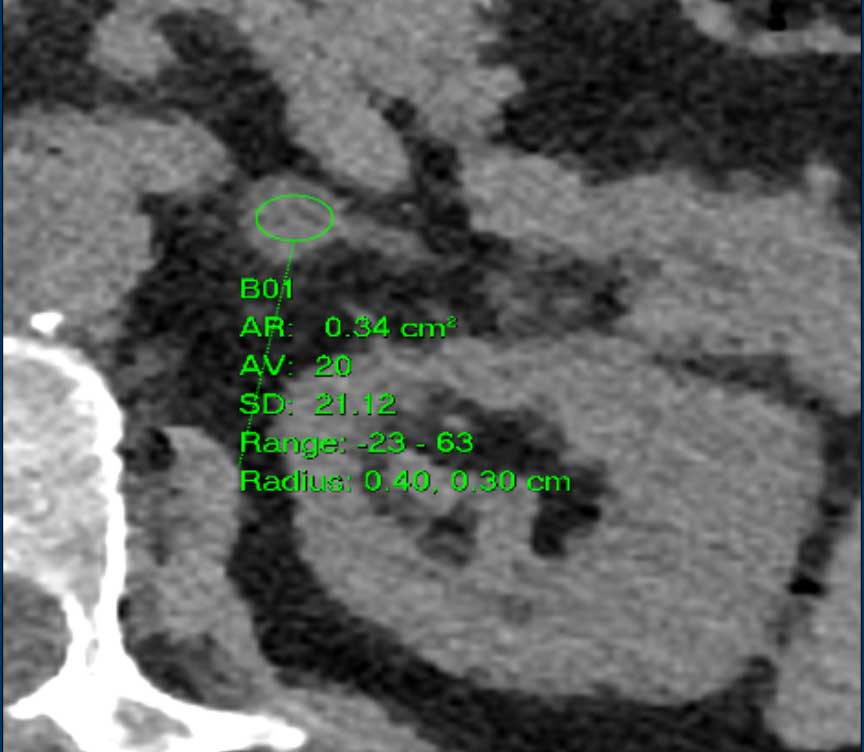

The images show bilateral adrenal incidentalomas found in a 64-year old patient scanned for analysis of an abdominal aneurysm.

The scan in the arterial phase shows bilateral lesions with a density of 50 HU.

On the non-enhanced CT performed a few days later, the density in both adrenal glands was less than 10 HU, proving these to be lipid-rich adenomas.